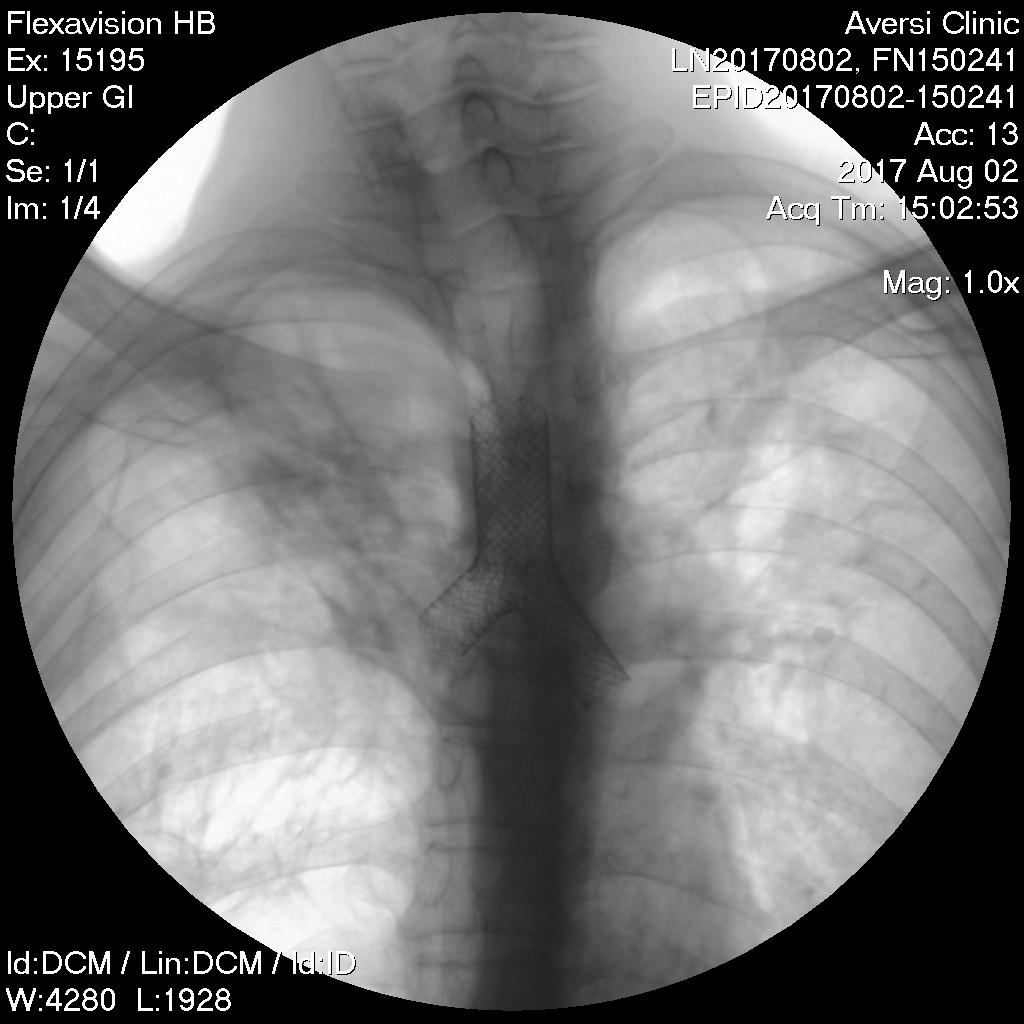

- CXR სტენტირების შემდეგ

პაციენტი 49 წლის მამაკაცი. 2007 წ-ს ჩაუტარდა ტუბსაწინააღმდეგო ქიმიოთერაპია ფილტვების ტუბერკულოზის გამო. 2015 წ-ს ჰქონდა რელაფსი. წლების განმავლობაში პაციენტს ჰქონდა ქოშინი, მზარდი სუნთქვის უკმარისობა, რის გამოც ხშირად საჭიროებდა ჰოსპიტალიზაციას. 2016 წლის სპირომეტრიული მონაცემებით ჰქონდა სასუნთქი გზების ობსტრუქციის მე-4 ხარისხი. გულმკერდის კტ კვლევით ინახა მკვეთრად დეფორმული ტრაქეობრონქული კუთხე, მარჯვენა ფილტვის ზედა წილში არსებული უხეში ფიბროზული ცვლილებები, ქვედა წილის უმეტეს ნაწილში გიგანტური ემფიზემატოზური ბულები, ხოლო მარცხენა მთავარი ბრონქის სანათურის შევიწროება 3 მმ-მდე. ბრონქოსკოპიულად ინახა მარცხენა მთავარი ბრონქის ნაწიბუროვანი სტენოზი. პაციენტის მდგომარეობა დღითიდღე უარესდებოდა, შეტევითი მოხრჩობის შეგრძნების გამო ხშირად უწევდა სასწრაფო დახმარების გამოძახება. გადაწყდა ტრაქეობრონქიალური სტენტირება, როგორც არსებული მდგომარეობიდან ერთადერთი გამოსავალი. ზოგადი ანესთეზიით, რიგიდული ბრონქოსკოპის გამოყენებით და რენტგენის კონტროლით განხორციელდა Braun 0,035 ვაიერების პასაჟი მარჯვენა და მარცხენა მთავარ ბრონქებში, შემდგომ გაიშალა ტრაქეობრონქიალური თვითგანშლადი სტენტი (M.D.-18mm;T.L.-40mm;L-14mmX25mm;R-14mmX25mm) ტრაქეასა და ორივე მთავარ ბრონქში. მანიპულაციის შემდეგ პაციენტის სუნთქვითი პარამეტრები საგრძნობლად გაუმჯობესდა. მანიპულაციიდან ერთი თვის შემდეგ თავს დამაკმაყოფილებლად გრძნობს.